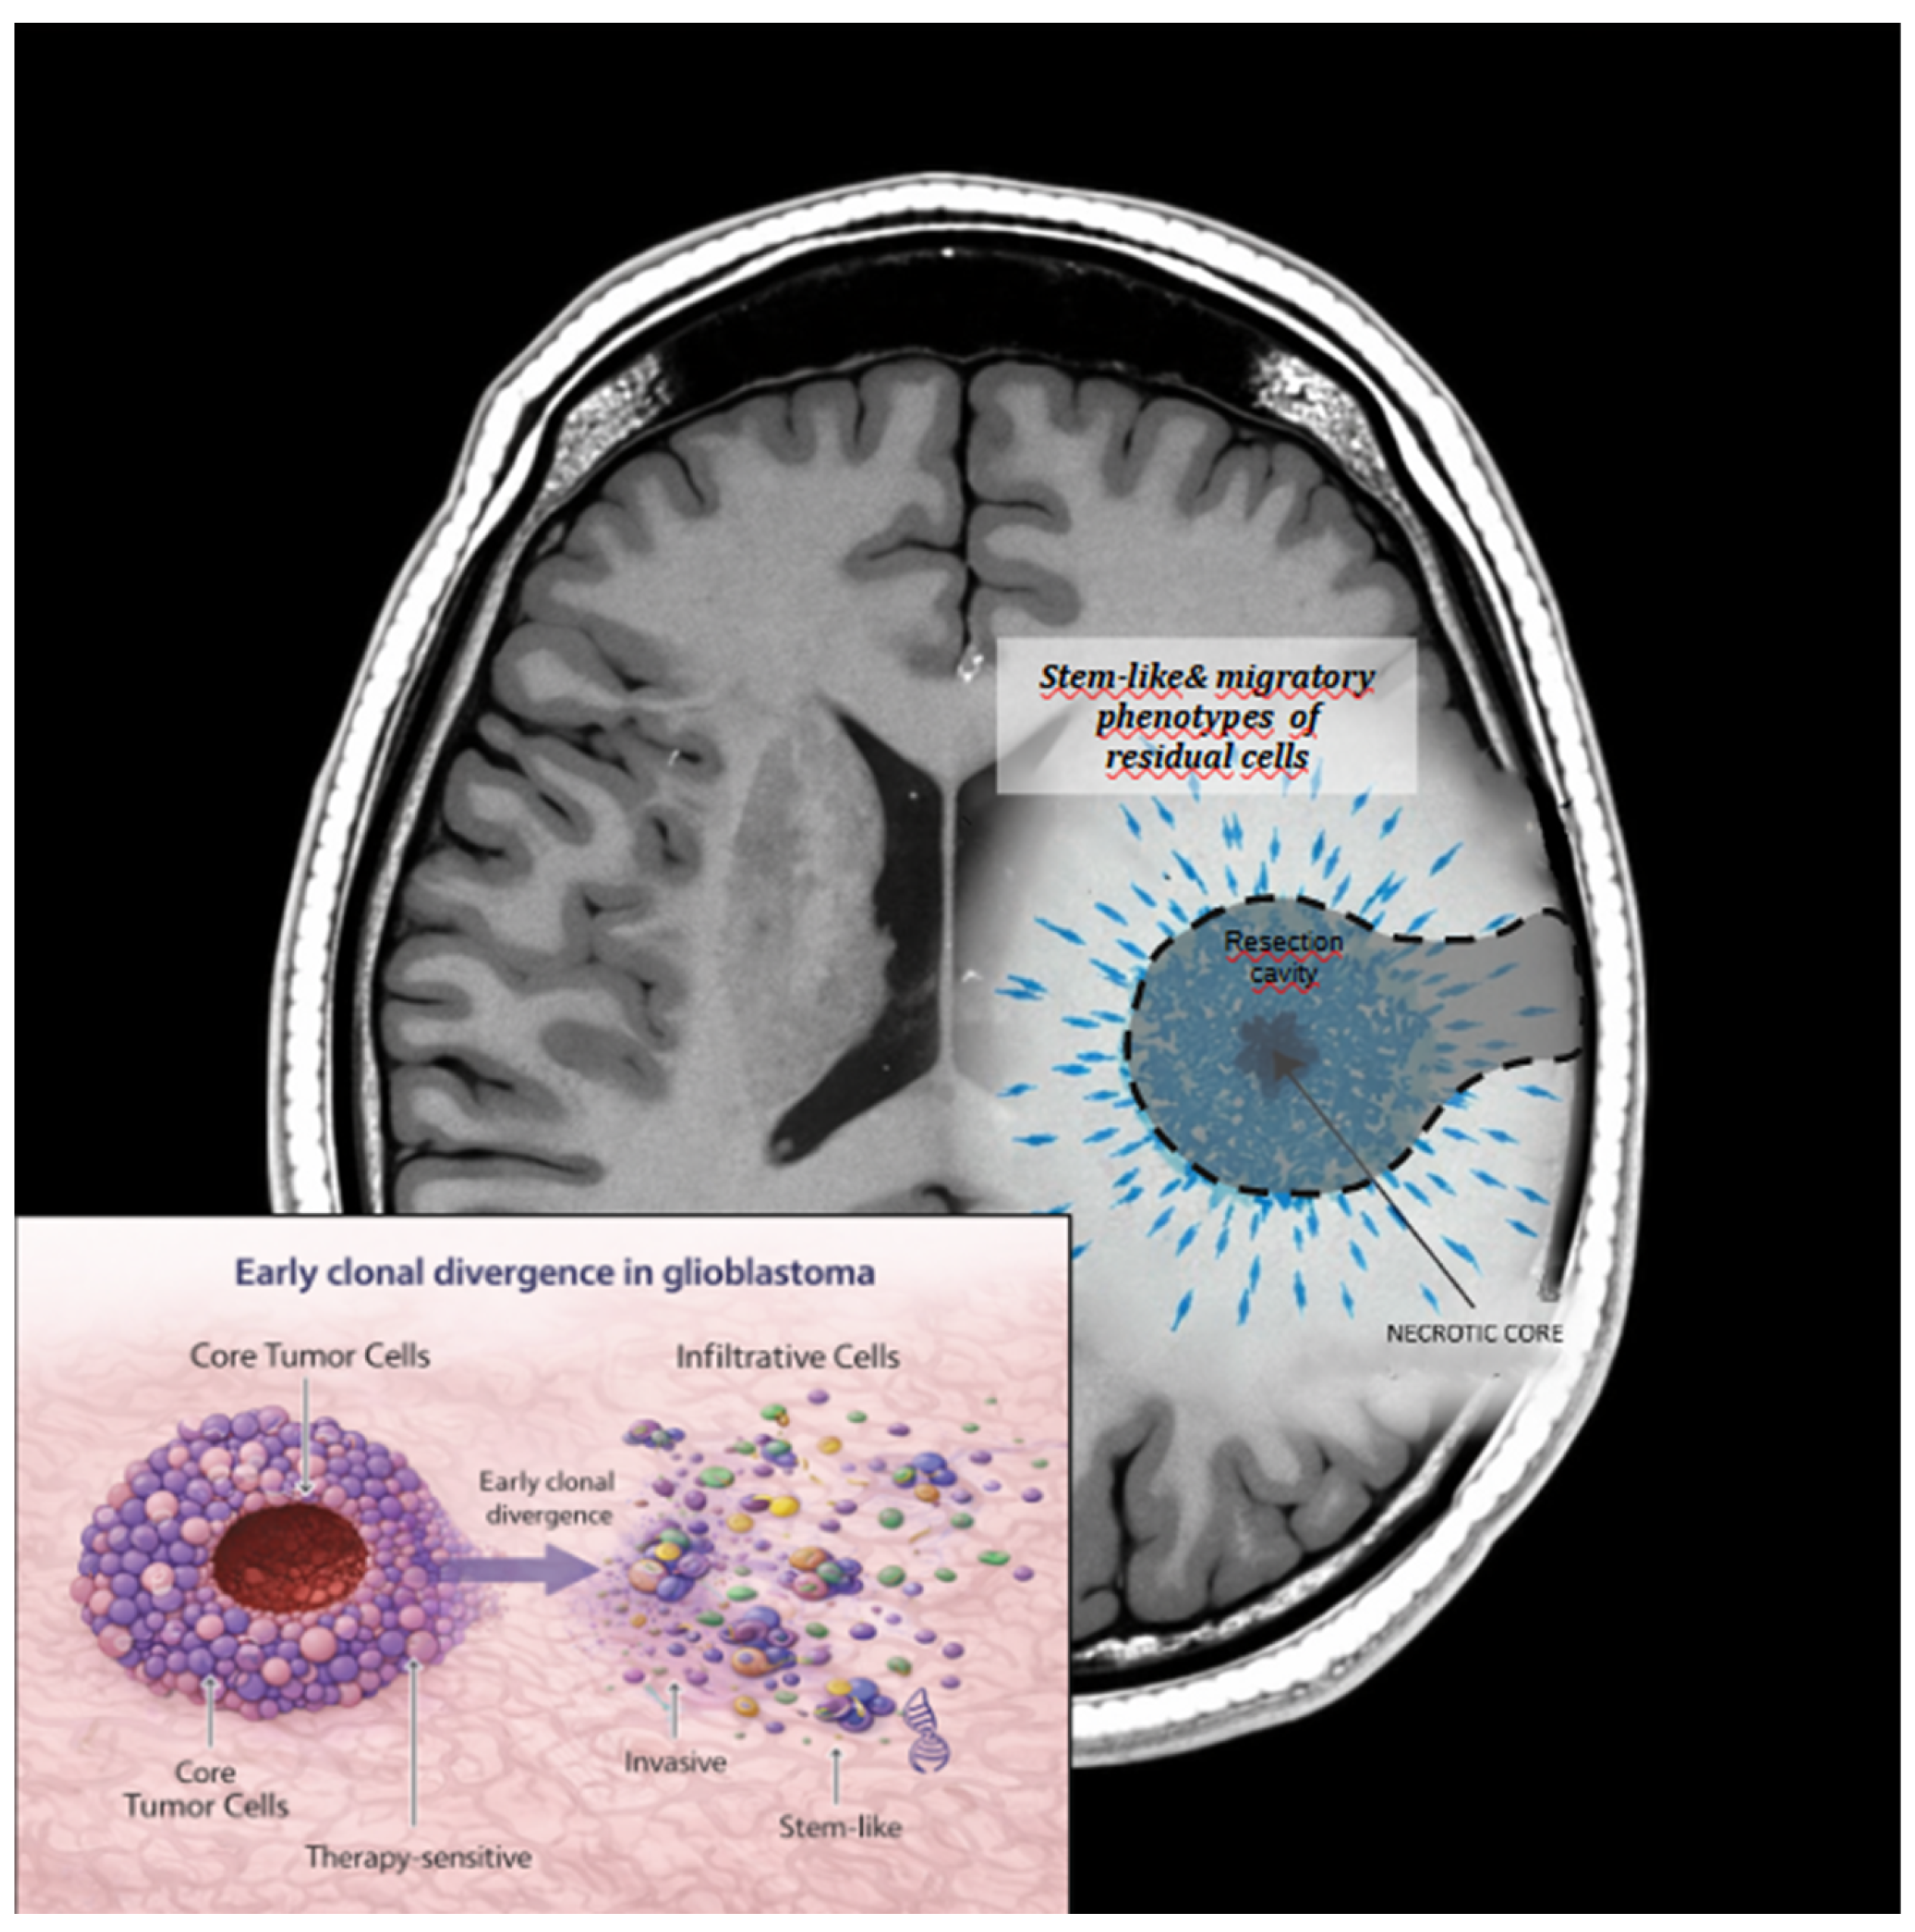

Collectively these findings support a model in which surgical resection acts as an evolutionary filter, selectively favoring tumor cell populations with enhanced adaptive capacity (Figure 2). The biological properties of the residual disease, rather than the absolute extent of resection, may therefore be critical determinants of recurrence pattern, aggressiveness, and response to adjuvant therapies. Recognizing surgery as a driver of clonal selection provides a conceptual framework for understanding why anatomically complete resections do not necessarily translate into durable disease control and underscores the need for postoperative strategies tailored to the evolving biology of residual tumor cells.

At the molecular level, residual tumor cells located at the invasive front often harbor distinct genetic and transcriptional profiles compared with cells from the tumor core. Bhaduri et al. [35] demonstrated that peripheral tumor populations exhibit stem-like and migratory phenotypes associated with treatment resistance. Similarly, Nomura et al. [36] identified transcriptional programs at the tumor-brain interface that promote invasion and adaptation, underscoring the biological relevance of marginal disease.

Collectively, these findings support a model in which surgery influences not only when and where tumors recur, but also how they recur at the molecular level. Recurrence should therefore be viewed as the outcome of an evolutionary process shaped by surgical cytoreduction, microenvironmental remodeling, and subsequent adjuvant therapies. As schematically summarized in Figure 4, the interplay between surgical margins, residual biologically active disease, and clonal evolution determines recurrence patterns and molecular progression.

Beyond the surgical margin, residual molecularly active disease may persist and drive local, marginal, or distant recurrence. Selective pressures induced by surgery and multimodal therapy promote clonal evolution, resulting in molecular and phenotypic shifts at recurrence, including stem-like features, invasiveness, therapy resistance, or new oncogenic drivers.

Figure 4. Schematic overview of glioblastoma recurrence biology.